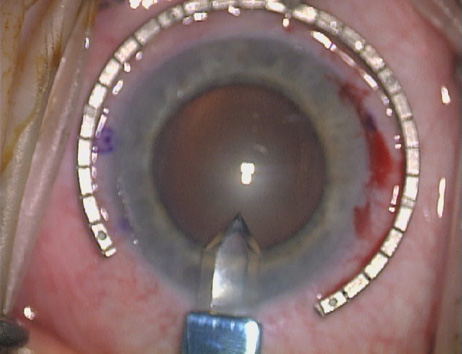

Case 2 is a 79-year-old woman who presented with a very dense left cataract. Her refraction was recorded at −2.25 +2.75 × 125 with a difficult end point. Her manual keratometry and topography measurements were consistent and revealed slightly less than 1.75 D at 120 degrees. Because of the questionable refraction, greater value was placed on the corneal measurements. Based upon the cataract nomogram, the plan was for paired LRIs of 40 degrees to be placed over the steep 120-degree axis (Figs. 1219).

Fig. 14. The incision is completed. (Reprinted from Hardten DR, Lindstrom RL, Davis EA. Phakic Intraocular Lenses: Principles and Practice. Thorofare, NJ: SLACK Incorporated, 2004, with permission.)

Fig. 15. Total arc length equals 40 degrees. (Reprinted from Hardten DR, Lindstrom RL, Davis EA. Phakic Intraocular Lenses: Principles and Practice. Thorofare, NJ: SLACK Incorporated, 2004, with permission.)